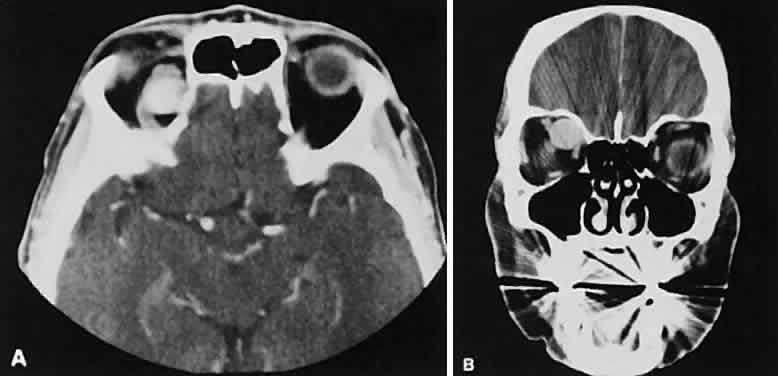

On most occasions, the inflammatory categories listed earlier are idiopathic and nonspecific. In-volvement of the adjacent paranasal sinuses should alert the clinician to the possibility of a systemic process such as Wegener's granulomatosis.34–38 Perioptic neuritis and trochleitis are the least common of the orbital inflammations. Clinically, perioptic neuritis shows signs of optic nerve dysfunction with pain and proptosis. The optic nerve may enhance, resembling acute optic neuritis39 or an optic nerve sheath meningioma.40 Inflammation of the trochlea presents with pain localized to the trochlea and can be associated with limitation of superior oblique muscle movement similar to a Brown's syndrome. Most patients are treated clinically without the benefit of CT scanning. One would expect an enhancing lesion centered on the trochlea. Calcification of the trochlea has been associated with advancing age; however, its presence, especially in those younger than 40 years of age, is strongly associated with diabetes.41 Graves' orbitopathy probably represents the most frequent cause of proptosis and EOM enlargement. The CT findings are fairly stereotyped and typically display various degrees of EOM enlargement (Fig. 7). The inferior rectus muscle usually is affected earliest, followed by the medial rectus, superior rectus, and finally the lateral rectus muscle. Rootman and colleagues13 noted more frequent involvement of the superior rectus/levator and medial rectus muscles than what had been reported previously with Graves' orbitopathy. These muscles can be affected in isolation, with the exception of the lateral rectus. To the best of our knowledge, isolated lateral rectus enlargement has not been reported in Graves' orbitopathy and in our experience usually is associated with a sphenoid wing meningioma. CT evidence of Graves' orbitopathy tends to be bilateral. Approximately 86% of patients with unilateral clinical findings have bilateral CT findings in our experience, which is consistent with the experience of others.42 Morphologically, the EOM belly is enlarged, with a gradual tapering toward and sparing of the tendinous portion of the muscle. Tendon involvement is a typical feature of orbital myositis. Tendon involvement helps to differentiate this lesion from Graves' orbitopathy, although Rootman and Nugent43 have noted a rare patient with Graves' orbitopathy with this finding. The muscle belly has a smooth contour with no edema of the adjacent orbital fat. We recently evaluated a patient with a referral diagnosis of Graves' orbitopathy. The patient was euthyroid but had severe orbital congestion typical of advanced Graves' orbitopathy. Imaging showed “dirty” orbital fat and lateral rectus muscle morphology that seemed atypical (Fig. 8). Biopsy specimen results showed a low-grade lymphoma. Hypertrophy of the medial rectus muscle can cause the medial wall to bow in toward the ethmoidal sinus from the chronic effects of pressure on the bone. The hypertrophied muscles also can give rise to a compressive optic neuropathy in the orbital apex as the enlarged muscles take their origin from the anulus of Zinn. Axial views of the apex show an apparent mass if the inferior rectus muscle is enlarged. It is imperative that additional views, sagittal or preferably coronal, be obtained to show the true nature of this apparent mass. Intracranial fat prolapse, seen by CT, may be another sign of optic neuropathy.44 An optic neuropathy also can be seen with relatively normal-sized EOM. An expanded fat compartment with optic nerve stretch has been associated with an optic neuropathy.45,46 Apical congestion/compression also may give rise to an enlarged SOV (see Table 1). If the veins appear asymmetric, the consideration of a carotid cavernous or dural sinus fistula should be entertained. Expansion of the orbital fat compartment also causes the orbital septum to bulge, an ancillary finding helpful in support of the radiographic picture of Graves' orbitopathy. We prefer CT scanning over MRI in the evaluation of patients with Graves' orbitopathy. Although there is no need to scan every patient, we do use imaging to corroborate the diagnosis of Graves' orbitopathy in instances of markedly asymmetric orbital involvement or any instance in which the diagnosis is in question. We also obtain a CT scan before orbital decompression to survey the paranasal sinus anatomy, to note the location of the infraorbital nerves giving an idea of how much floor is available for decompression, and, most important, to use the direct coronal views for inspection of the cribriform plate, which identifies patients at risk of having cerebrospinal fluid leaks.8 |